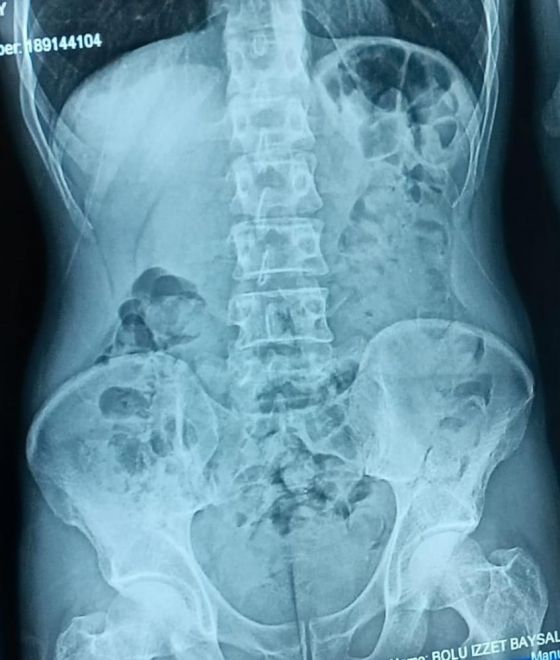

Edinilen bilgiye göre, İl Emniyet Müdürlüğü Narkotik Suçlarla Mücadele Şube Müdürlüğü ekipleri, doğu illerinden İstanbul’a seyir halinde olan yolcu otobüsünde uyuşturucu madde taşındığı ihbarı üzerine çalışma başlattı. Ekipler, il sınırına girdiği tespit edilen yolcu otobüsünü uygulama noktasında durdurdu. Otobüste bulunan yolculardan Şefik B.’nin eliyle karnını tuttuğu ve şüpheli hareketleri olduğunu gören ekipler, şahsı olay yerinde sorguladı. Yapılan sorgusunda midesinde kapsül halinde uyuşturucu madde olduğunu itiraf eden Şefik B., hastaneye götürülerek mide röntgeni çekildi. Röntgende midesinde çok sayıda kapsül tespit edilen Şefik B.’nin, 48 parça halinde 542 gram eroini doğal yollarla çıkarması sağlandı.